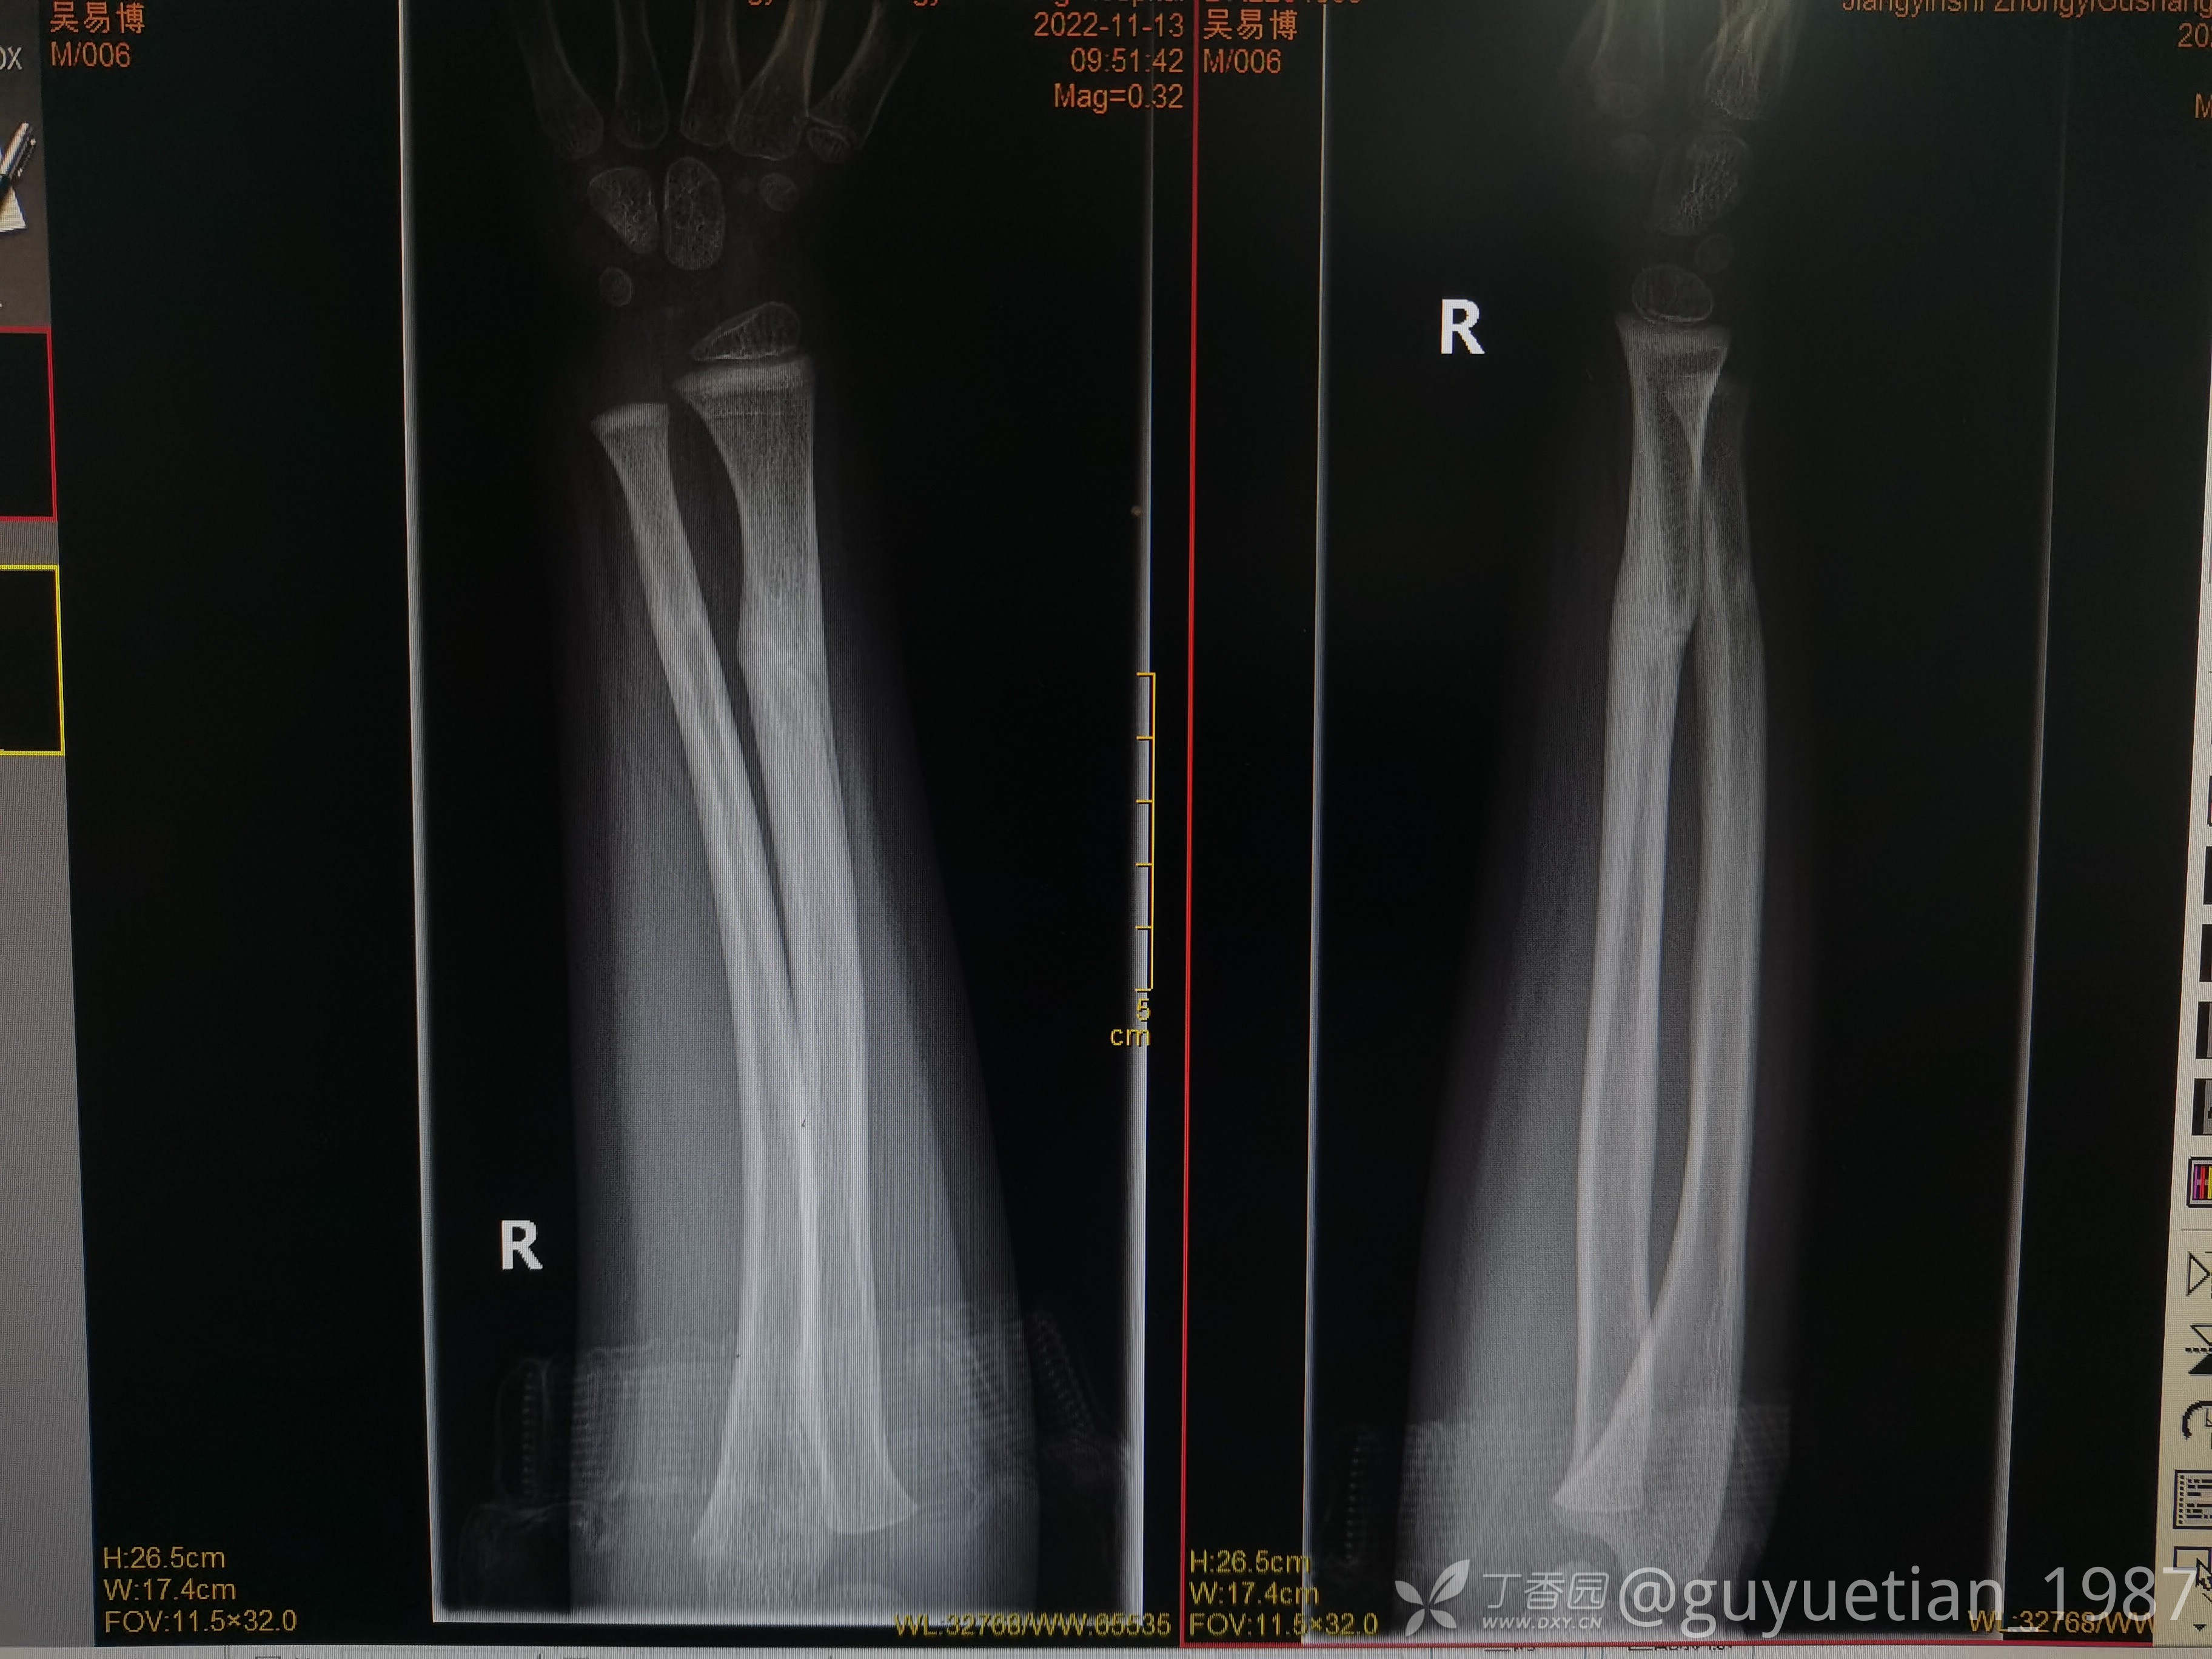

2月余复诊,基本完全塑形

信任永远是医患的基础,用心认真对待每个愿意相信你的病患。